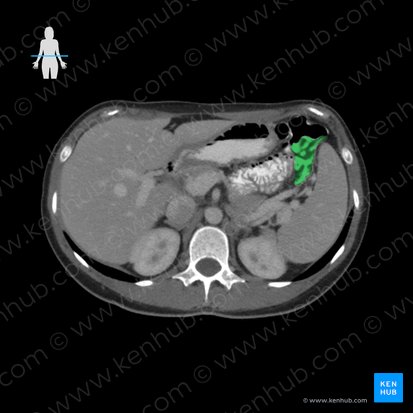

Descending colon

The descending colon is a segment of the large intestine positioned within the left paracolic gutter of the posterolateral abdominal wall. It extends from the left hypochondriac region and runs through the left flank to reach the left iliac fossa. Beginning at the left colic flexure proximally, it descends vertically and becomes continuous with the sigmoid colon distally.

In adults, the descending colon measures about 25–30 cm. It is a retroperitoneal organ, with its anterolateral surface covered by parietal peritoneum that attaches it to the posterior abdominal wall. It runs anterior to the lateral border of the left kidney and in about a third of people, the distal portion of the descending colon has a short mesentery.